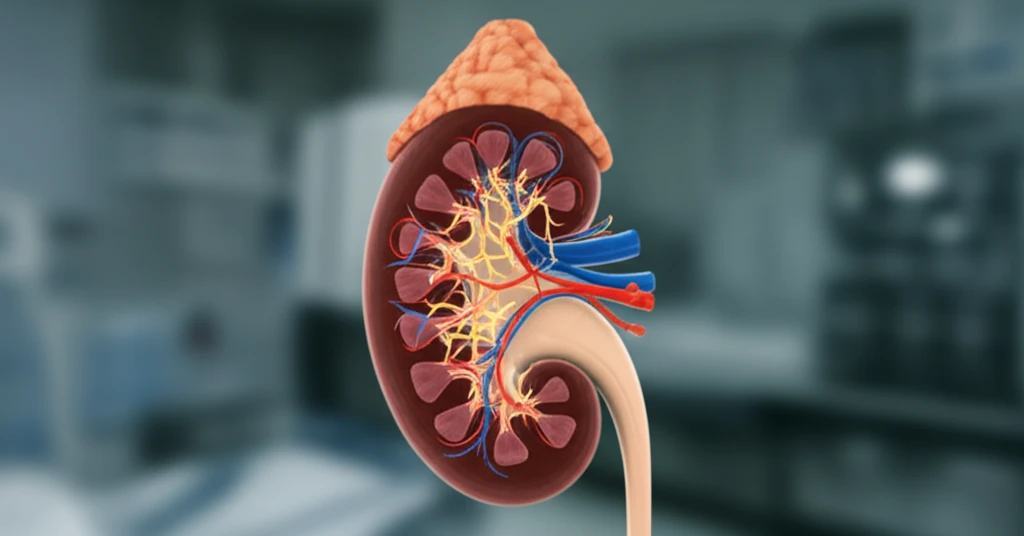

Myxoma, a rare benign tumor, commonly develops in various parts of the body like the skin, bones, and viscera. However, its presence in the kidney is exceedingly rare. When it does occur in the kidney, it typically resides in the parenchyma, with only a few cases involving the capsule.

In summary, renal myxoma is a rare benign mesenchymal tumor that requires careful diagnostic evaluation and management. Advanced imaging techniques, such as CT and MRI, play a crucial role in identifying and characterizing these lesions. While nephrectomy has been the standard approach due to malignancy concerns, this case highlights the potential for kidney-sparing approaches when a benign diagnosis is confirmed. Continued research and awareness are essential to optimize outcomes for patients with this rare condition.